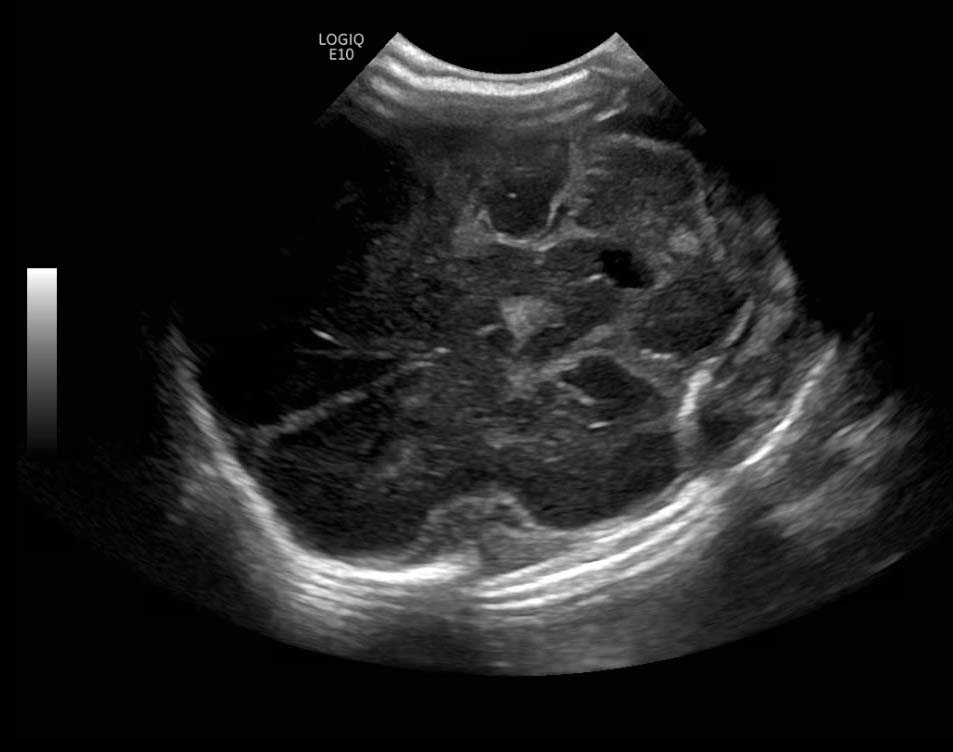

Age: 4 days (born at 24 weeks)

Sex: Male

Indication: Evaluate for germinal matrix hemorrhage

Grade 2 germinal matrix hemorrhage

Sample ReportLeft germinal matrix hemorrhage involving the caudothalamic groove and layering in the occipital horn of the left lateral ventricle without hydrocephalus (grade 2).

No abnormal brain parenchymal echogenicity or extra-axial collections.

Premature sulcation pattern.